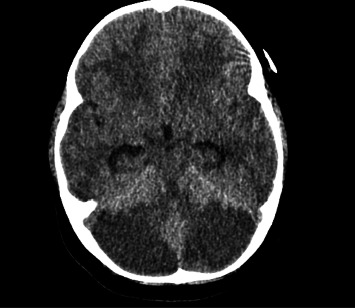

美沙酮是一种用于治疗疼痛和阿片类药物依赖的合成阿片类药物。尽管它的好处,意外摄入美沙酮在儿科患者可导致显著的发病率和死亡率。儿童摄入美沙酮引起的急性毒性包括脑白质病和小脑炎。对儿童美沙酮过量后的治疗和影响临床结果的因素的研究有限。我们报告一个3岁的儿童严重脑损伤和死亡后意外摄入美沙酮。我们的病例是独特的,因为我们能够获得摄取后的血清美沙酮水平,这是用来指导干预和治疗。通过这个案例,我们的目的是促进对美沙酮毒性的日益了解,同时也倡导实施保护我们儿科人口的政策。

Methadone is a synthetic opioid used to treat pain and opioid dependence. Despite its benefits, accidental ingestion of methadone in pediatric patients can lead to significant morbidity and mortality. Documented findings of acute toxicity secondary to methadone ingestion in children include leukoencephalopathy and cerebellitis. There is limited research into treatment and factors influencing clinical outcomes following methadone overdose in children. We report a 3-year-old child with severe brain injury and death following accidental ingestion of methadone. Our case is unique in that we were able to acquire a serum methadone level following ingestion, which was used to guide intervention and treatments. Using this case, we aim to contribute to the growing understanding of methadone toxicity while also advocating for the implementation of policies that protect our pediatric population.